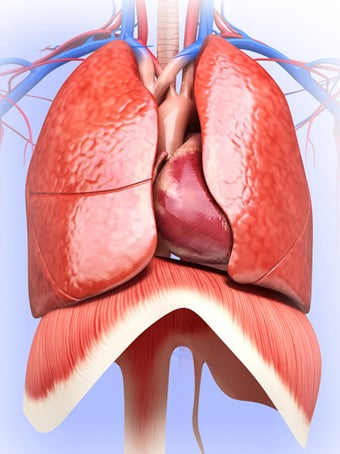

呼吸器系の解剖学は、肺、気管、およびすべての気道を含む呼吸器系の解剖学の研究です。最も一般的なアプローチは、系を上部と下部に分割することです。上部には気管、主気管支、および終末および前頸気道が含まれます。下部には肺と最小の大きさの末梢気道が含まれます。これらの部分それぞれには特徴的な外観と機能があります。